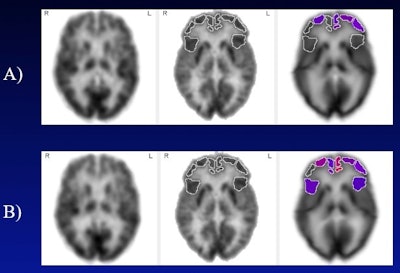

(A) Frontal cortical regions with below-normal metabolism (less than 5th percentile, displayed in color) at baseline, in subject with mild cognitive impairment and untreated hearing loss. (B) Frontal cortical regions with below-normal metabolism two years later. Brighter red colors correspond to more severely diminished metabolism. In contrast, the group of subjects using hearing aids did not undergo significant decline in any frontal cortical region over the same time period. Image courtesy of Natalie Quilala.

Over one year, the most significant differential metabolic decline occurred in the left superior frontal gyrus when comparing the control group against the untreated hearing loss group, according to the findings. The hearing aids group against the control group yielded a significant differential decline in left superior frontal gyrus as well (p = 0.02), while the hearing loss group declined 1.5 times faster than the hearing aids group, Quilala reported.

After two years, the untreated hearing loss group had significant declines against the control group in the right mid-frontal gyrus (p = 0.007), the right posterior inferior frontal gyrus (p = 0.01), and left inferior frontal gyrus (p = 0.04). In contrast, during the same period of time, the hearing aids group had no significant decline in metabolic rate in these or any other of the 47 brain regions examined.